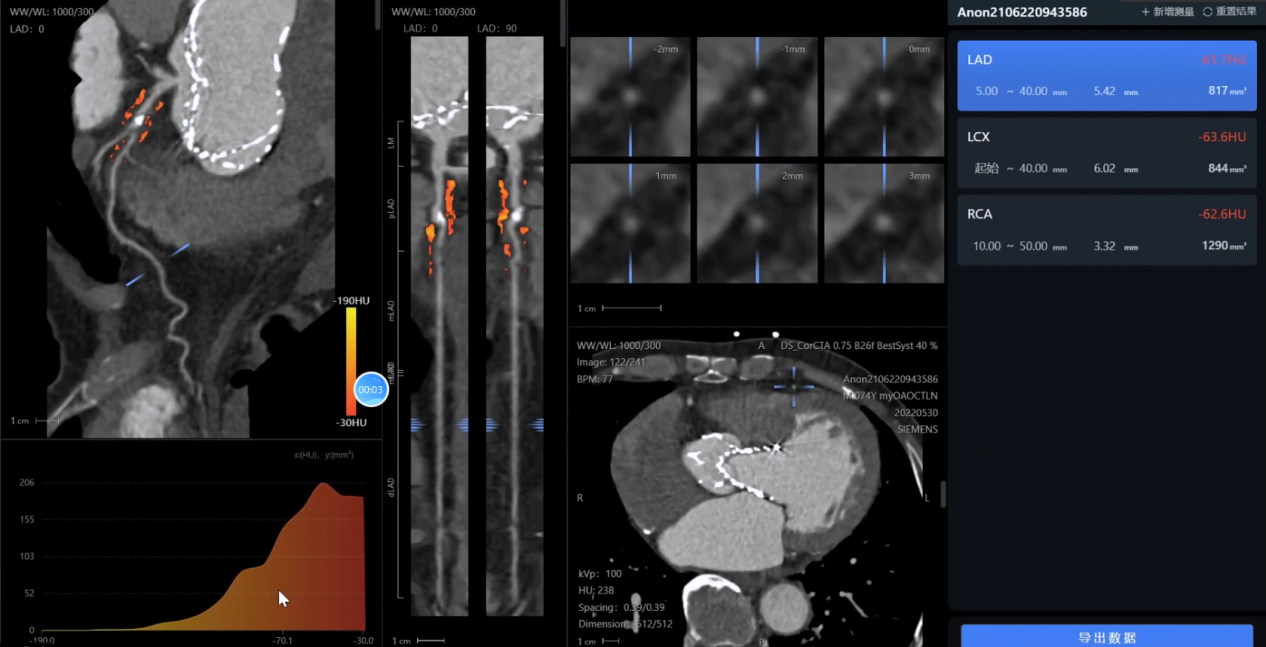

影像分析方面:系統(tǒng)能夠自動(dòng)處理心血管CTA、腦血管MRA、外周血管超聲等多模態(tài)影像數(shù)據(jù),精準(zhǔn)識(shí)別斑塊性質(zhì)、狹窄程度和病變范圍,生成結(jié)構(gòu)化報(bào)告。

綜合評(píng)估方面:啄醫(yī)生大模型整合患者臨床資料、實(shí)驗(yàn)室檢查和影像學(xué)結(jié)果,構(gòu)建個(gè)體化的泛血管健康指數(shù),全面評(píng)估全身血管健康狀況。